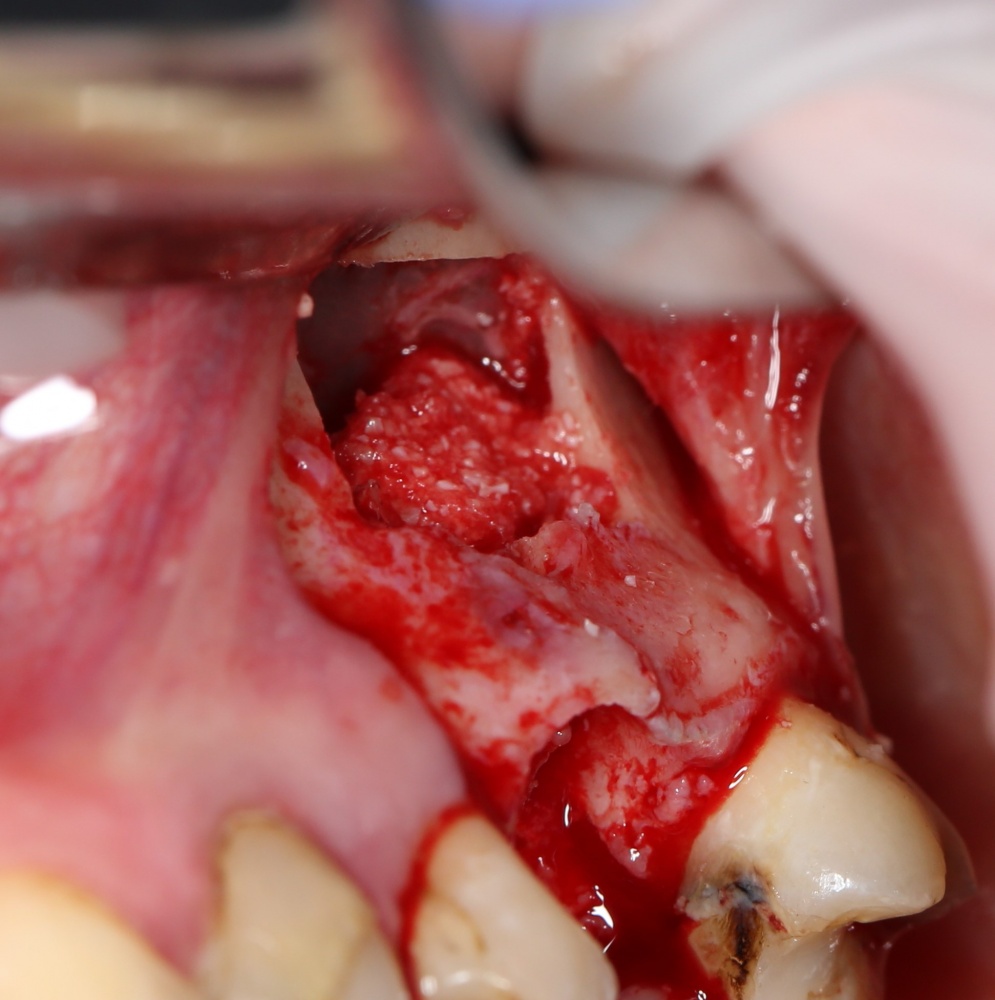

Простой синуслифтинг. Часть I.